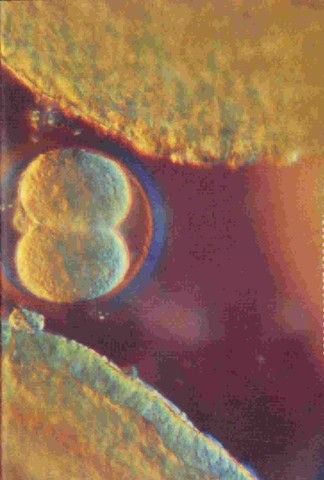

Title picture

First round of mitosis (cleavage)

Second round of mitosis

Third round of mitosis